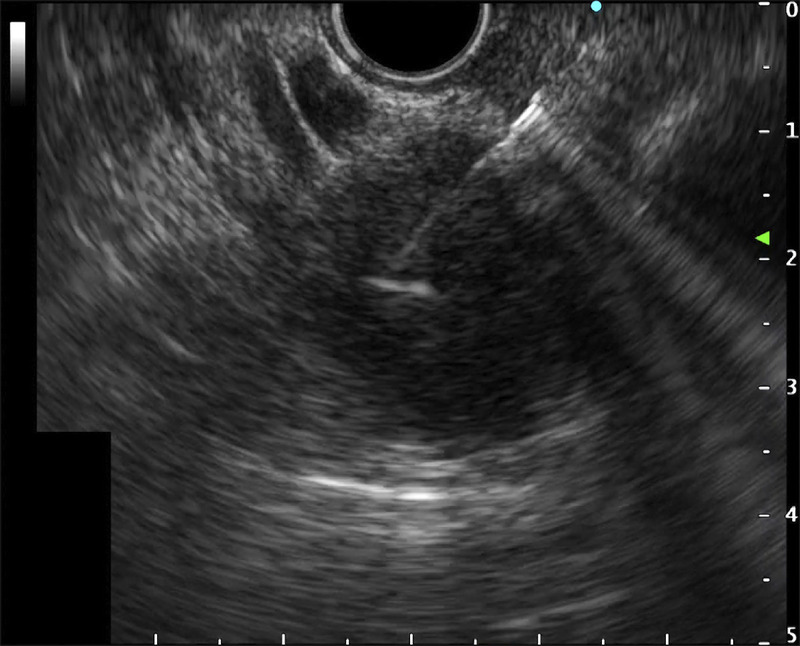

Abstract Image